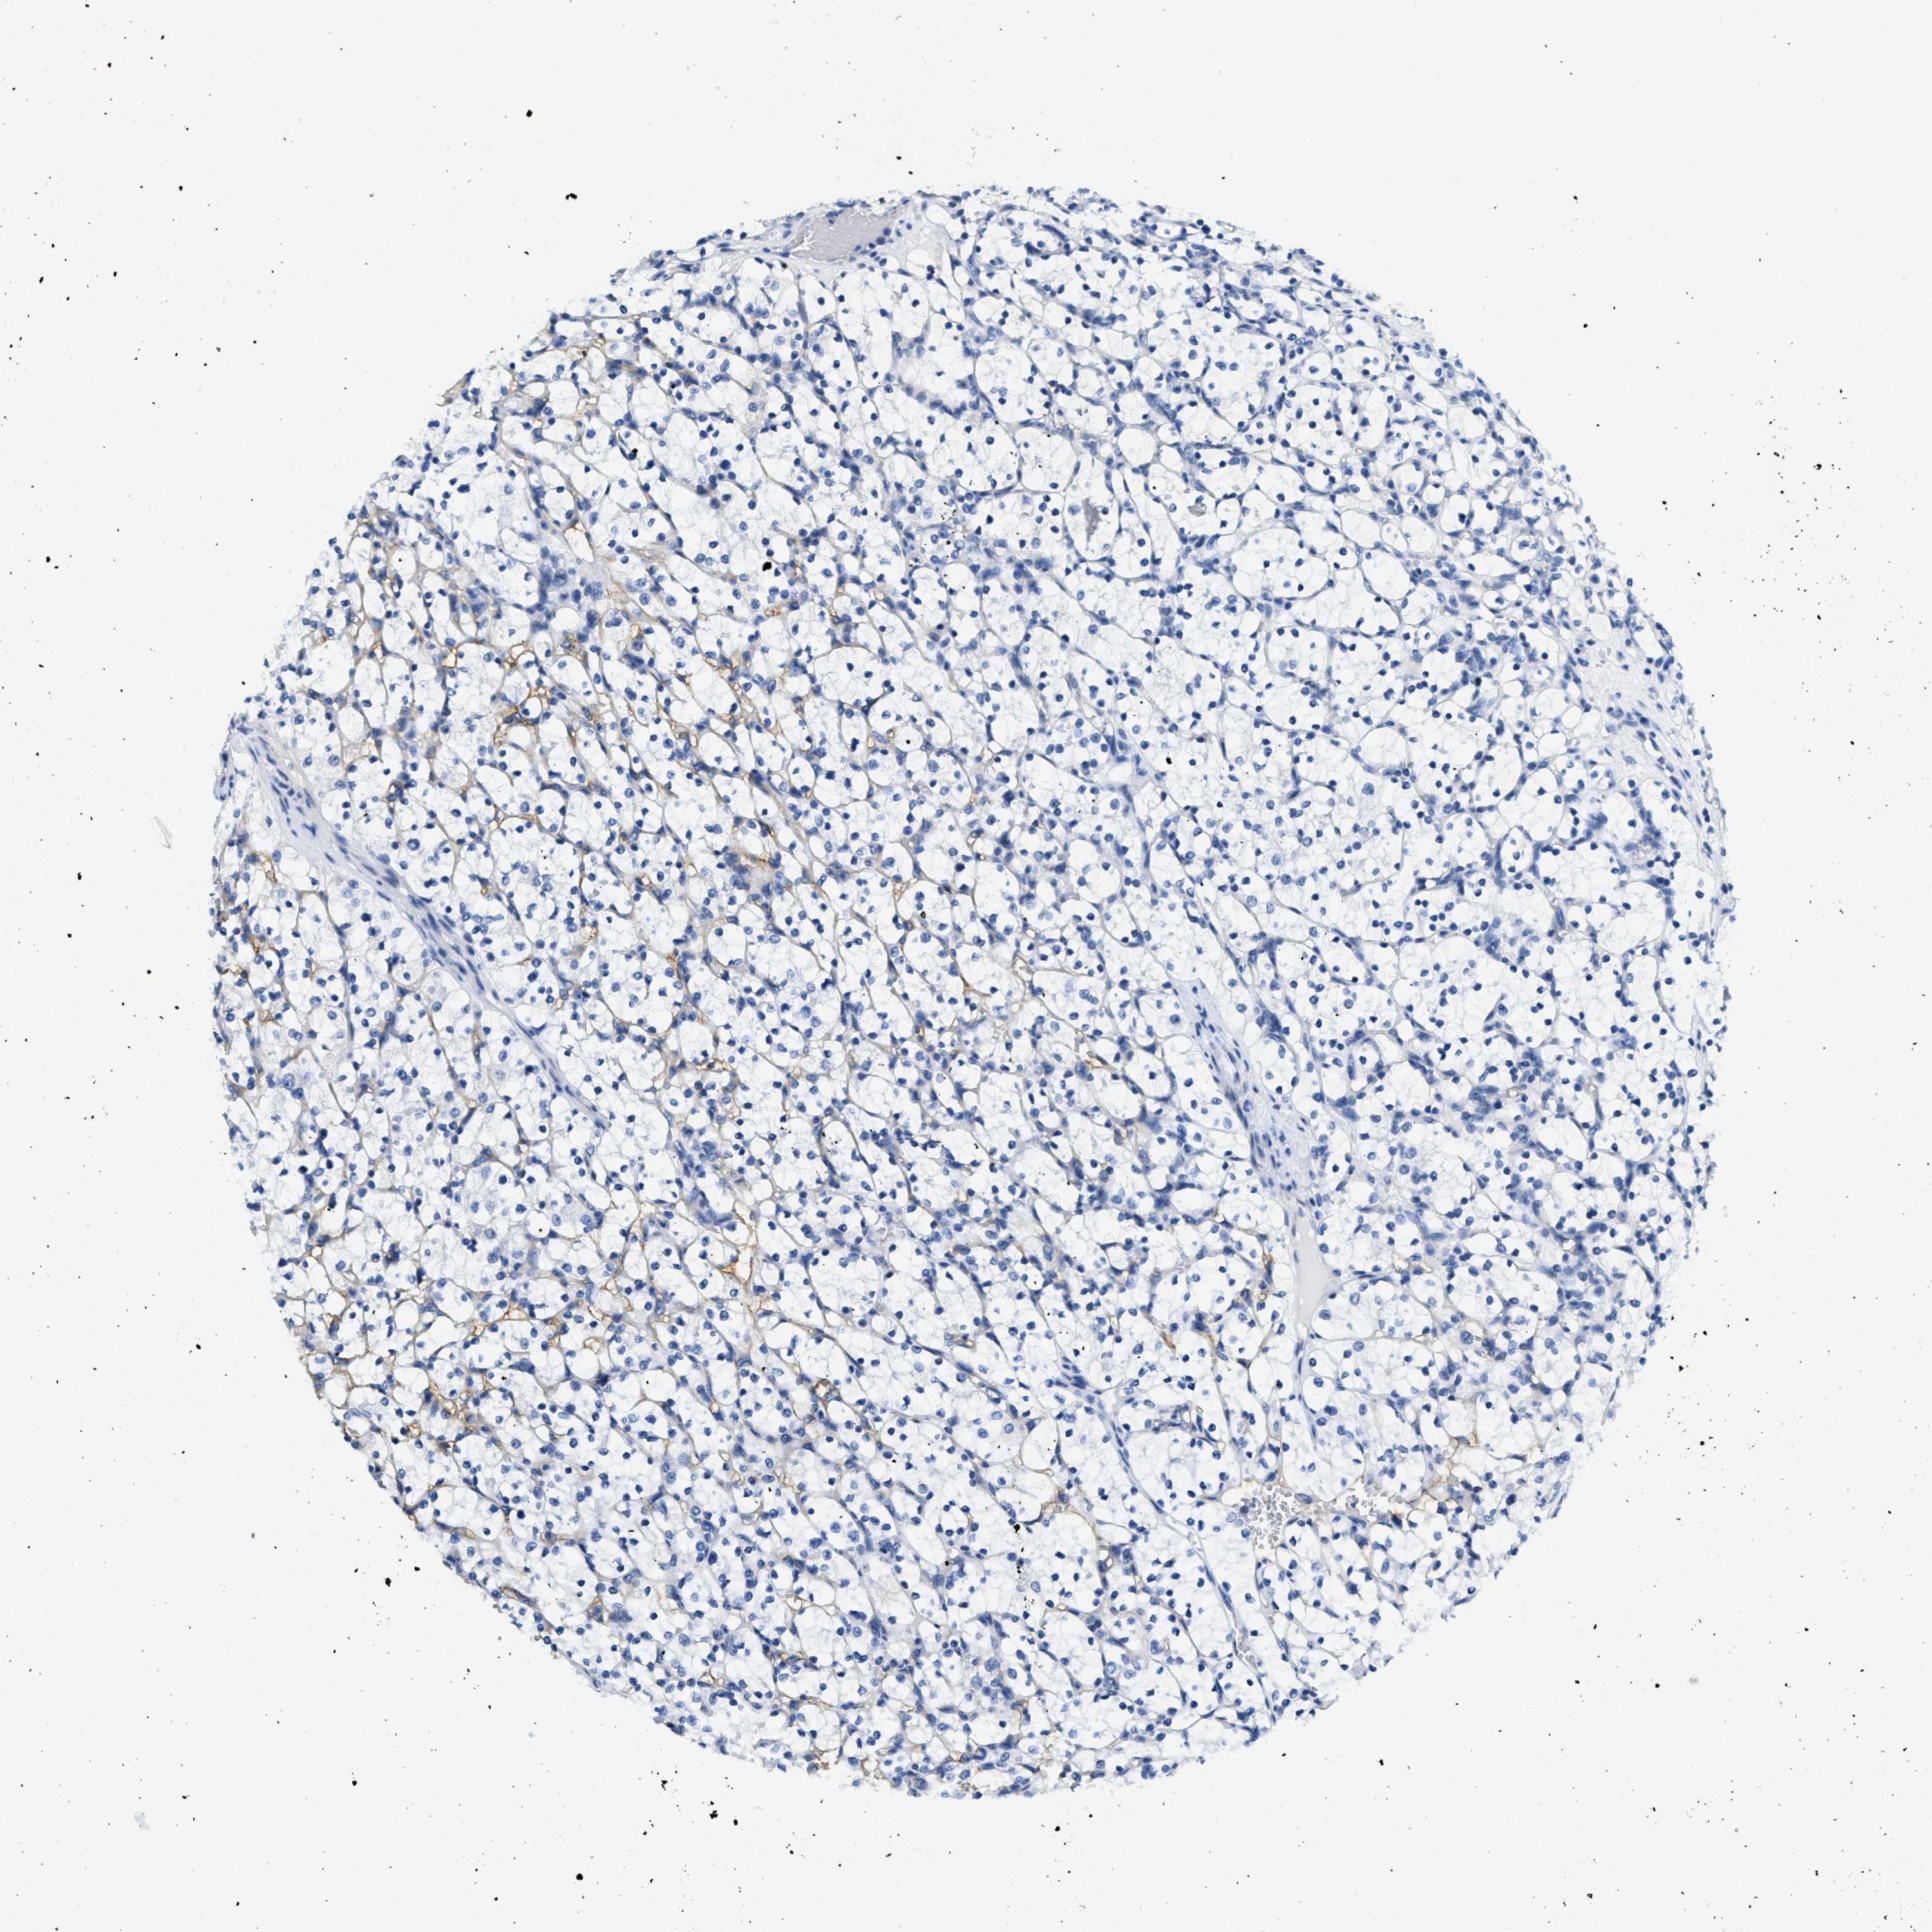

KIDNEY RENAL CLEAR CELL CARCINOMA (VALIDATION) - Interactive survival scatter ploti

The Survival Scatter plot shows the clinical status (i.e. dead or alive) for all individuals in the patient cohort, based on the same data that underlies the corresponding Kaplan-Meier plots. Patients that are alive at last time for follow-up are shown in blue and patients who have died during the study are shown in red.

The x-axis shows the expression levels (FPKM) of the investigated gene in the tumor tissue at the time of diagnosis. The y-axis shows the follow-up time after diagnosis (years). Both axes are complimented with kernel density curves demonstrating the data density over the axes. The top density plot shows the expression levels (FPKM) distribution among dead (red) and alive patients (blue). The right density plot shows the data density of the survived years of dead patients with high and low expression levels respectively, stratified using the cutoff indicated by the vertical dashed line through the Survival Scatter plot. This cutoff is automatically defined based on the FPKM cutoff that minimizes the p-score. The cutoff can be changed by dragging the vertical line or by entering a cutoff value in the square labeled "Current cut-off".

Under the Survival Scatter plot the p-score landscape (black curve; left axis) is shown together with dead median separation (red curve; right axis). Dead median separation is the difference in median mRNA expression between patients who have died with high and low expression, respectively. It is calculated as follows: median FPKM expression of dead patients with high expression - median FPKM expression of dead patients with low expression. This is intended to aid the user in visually exploring custom cutoffs and the associated p-scores and dead median separation.

Individual patient data is displayed and can be filtered by clicking on one or more of the category buttons on the top of the page. Categories describing expression level and patient information include: high, low, alive, dead, female, male and tumor stages. The scale of the x-axis can be toggled between linear and log-scale by clicking on the "x log" button. Mouse-over function shows TCGA ID, patient information and mRNA expression (FPKM) for each patient.

& Survival analysisi

Kaplan-Meier plots summarize results from analysis of correlation between mRNA expression level and patient survival. Patients were divided based on level of expression into one of the two groups "low" (under cut off) or "high" (over cut off). X-axis shows time for survival (years) and y-axis shows the probability of survival, where 1.0 corresponds to 100 percent.

CA4 is validated prognostic, high expression is favorable in Kidney Renal Clear Cell Carcinoma (validation)

: 1.39

Average pTPM 12.8

Number of samples 100